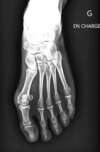

Le diagnostic de l'hallux valgus est clinique : le simple examen permet de faire le diagnostic. Toutefois une radio du pied en appui est nécessaire pour en apprécier le caractère évolutif, les déformations osseuses associées au niveau des métatarsiens et orteils latéraux, la présence ou non d'une arthrose etc...

Hallux Valgus avant pied Gauche : forme majeure du sujet âgé

-

Côté droit déjà opéré de la même déformation 1 an plus tôt

Même patiente : bilan radiographique

Chirurgie 1 an plus tôt côté droit

Hallux Valgus avant pied gauche : radiographie en charge de Face